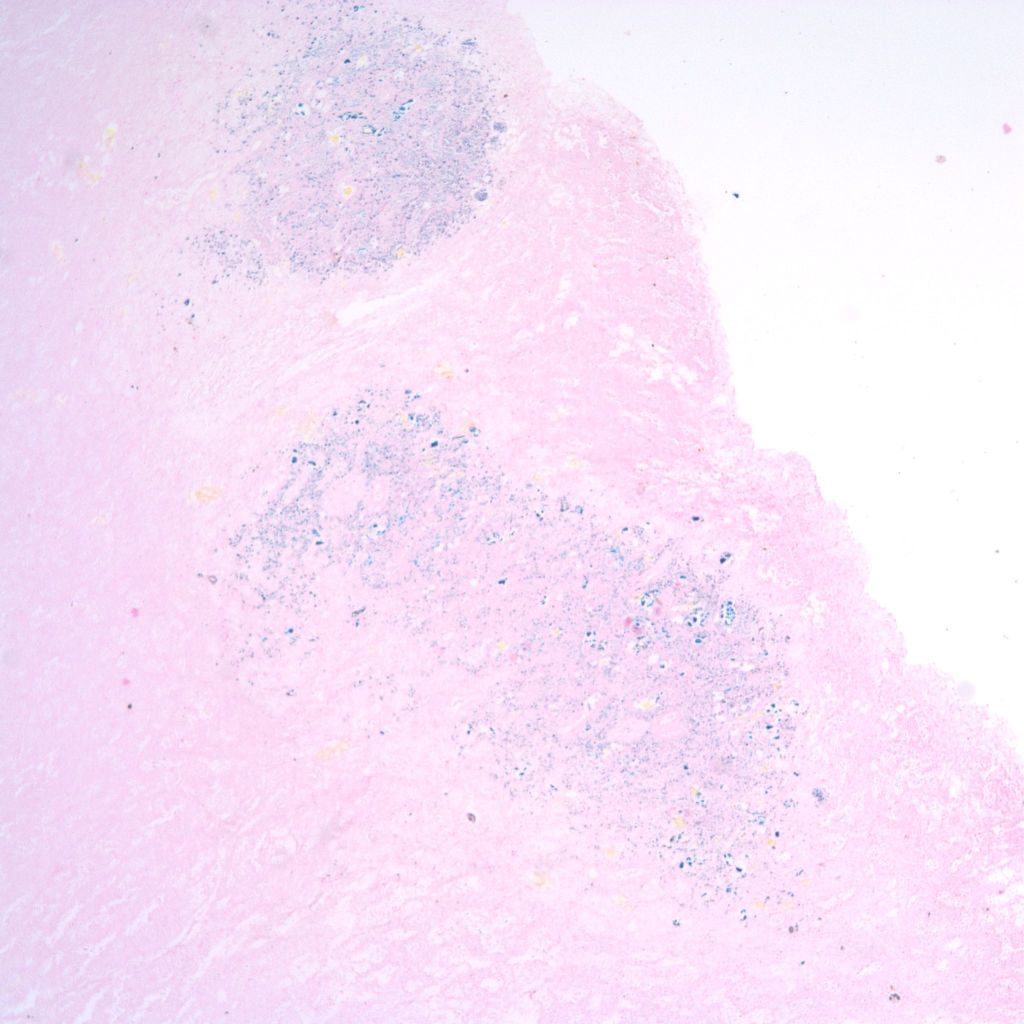

In severely autolytic lung, the distinction between intrinsic hemorrhage and aspirated blood may not be discernable with only iron staining for hemosiderin to trace the vestige of the hemorrhage (Fig 24).